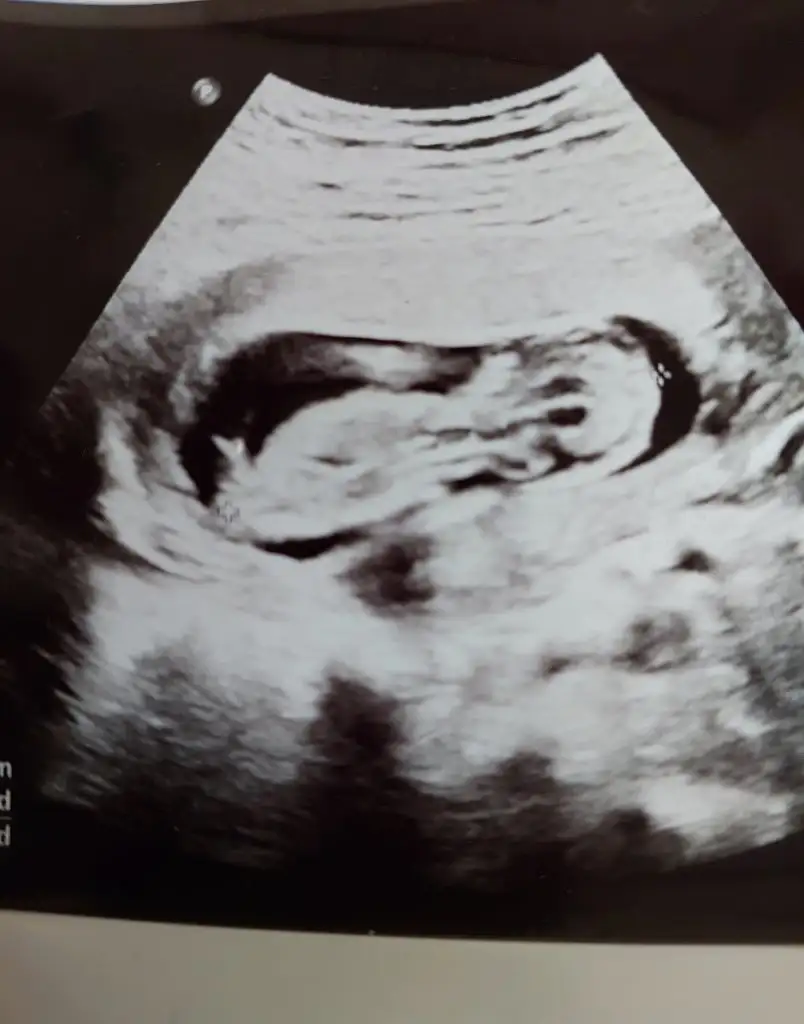

9+3 :)Kızlar bebişlerinizin ultrason resimlerini ve cinsiyetini kaçıncı haftada olduklarını yazında kendi ultrason resimlerimizle kıyaslayıp fikirde bulunalım. Nub teorisi, kafa şekli, kemik yapısından cinsiyet teorileri tutuyor mu bakalım bir![]()

Benimkimede bakarmısınız 7 haftalığızKızlar bebişlerinizin ultrason resimlerini ve cinsiyetini kaçıncı haftada olduklarını yazında kendi ultrason resimlerimizle kıyaslayıp fikirde bulunalım. Nub teorisi, kafa şekli, kemik yapısından cinsiyet teorileri tutuyor mu bakalım bir![]()